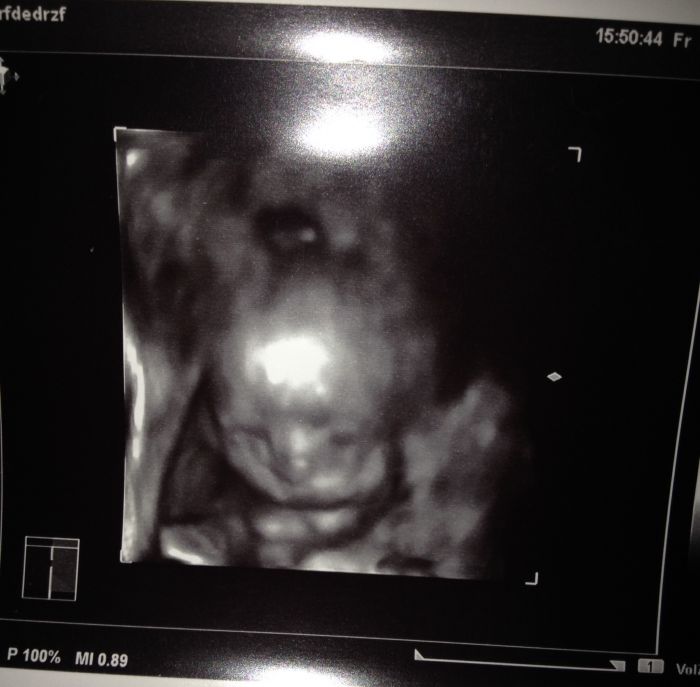

Ahojky holky,byla jsem tu naposledy pred měsícem, tak jsem se prisla mrknout co nového. Jinak ted jsem 21+5 tt a uz cítím docela dobre kopanecky:)krasnej pocit. Uz mame i pravidelný intervaly, tak se vždy těším na určitou hodinu a čekám :). Na velkém utz jsem uz take byla, akorat me trošičku postrasili, ze na miminko neco na srdicku(focus) a musím ted 14 dni čekat na výsledky a pak se uvidí:( nemáte s tím nějaká zkušenost? Nevim co od toho čekat...jsem docela vyplasena:(..dělohu mam take porad pod pupkem a to jsem 22 tt. Tak snad bude vse ok. Zavolám nějaké fotecky miminka:)

jé, krásná fotečka :)